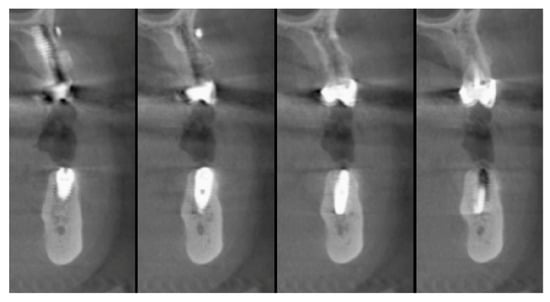

The vertical average defect was 9.16 mm, buccal lateral/palatal 7.0 mm, and mesio-distal 10.3 mm. The measurements were intraoperatively performed with a millimeter periodontal probe. The endodontic material mechanically cleaned before the tooth was placed inside the Tooth Transformer device. The endodontic material was removed using a drill bur with the attention to cut the canal in excess with the aim to remove all the cement. No surgical complications were registered. Pre and post-operative X-rays (section from CBCT) were collected from the same case (Figure 1, Figure 2, Figure 3 and Figure 4). After four months, 13 histological and histomorphometrical evaluations were performed (Figure 5). The Bone Volume/Total Volume average (BV%) was 41.47 (S.D. ± 11.51), the Residual Graft/Total Volume average (Graft%) was 16.60 (S.D. ± 7.09), and the Vital Bone/Total Bone average (VB%) was 21.89 (S.D. ± 9.72). No extraneous material (gutta-percha or cement) was detected in all samples (Table 3).

Figure 1. X-ray, elements 35 and 36 surrounded by a big bone defect.

Figure 2. In the cbct section in zone 36, it is possible to note the bone loss dimension.